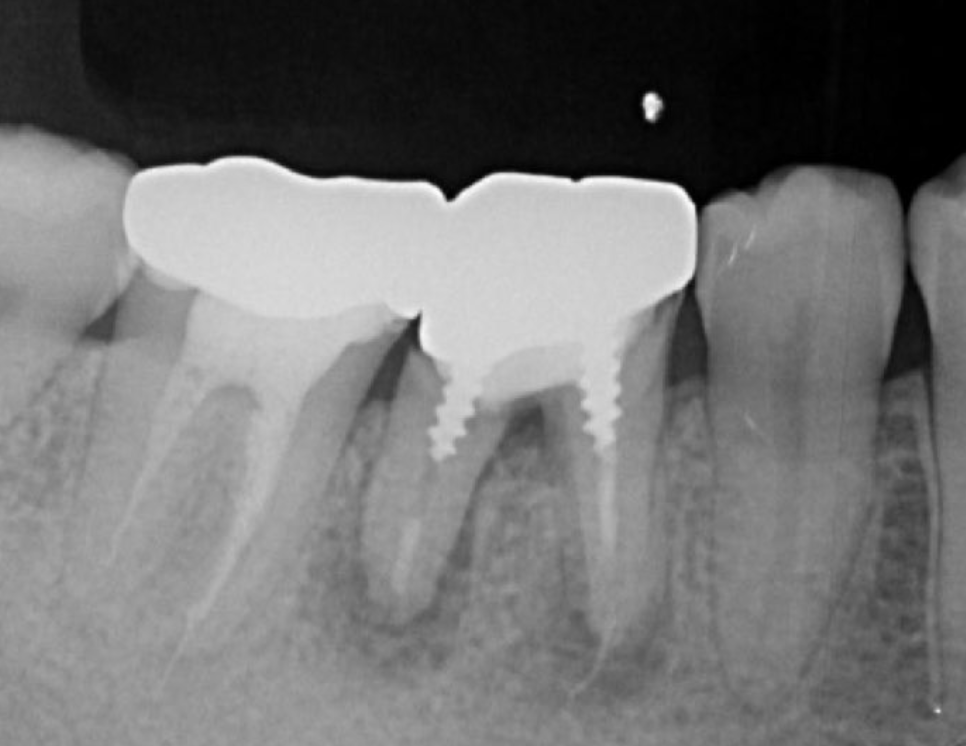

A 27-year-old female patient came to us with discomfort in the right lower jaw (Figure 1). Her primary symptoms were pain in the lower right tooth when biting and discomfort associated with not being able to chew well with the lower left single denture. The patient was married and had one young child, and previously received dental treatment in China, then had returned to Japan for childbirth and early childcare. The patient was a nonsmoker with moderate plaque control and medical history taking revealed no problems. In clinical and radiographic examinations, a root fracture was observed on tooth #46, which had been endodontic ally treated and restored with a full-cast metal crown. Periodontal probing revealed a pocket depth of 8 mm on the buccal center side of the tooth. No pain was detected with percussion and mobility of the tooth was normal. (Figure 1, Figure 2, Figure 3).

Figure 1.Clinical case of right auto transplantation. Panoramic view at initial examination.Tooth #46 was shown to be half decayed and a cystic lesion was found in the mesial root apex. Tooth #36 was lost, while #48 and #38 were present. There was a total of 29 teeth in the oral cavity.

Figure 2.Pre-treatment X-ray findings. A cystic lesion was found in the mesial and distal roots apex, and root nodule of #46.

The transplantation process begins with a surgical procedure according to the following requirements; the recipient site should be prepared according to the donor tooth shape, time needed for recipient site preparation should be minimized, the number of fitting attempts using the donor tooth should be as few as possible, and extraction of the donor tooth should be gently performed. For realization of an ideal surgical setting, panoramic X-ray and CBCT results (Fig. 1-9) are essential for preoperative diagnosis. In the present case, root completeness, Moorrees classification 18, and donor tooth size were determined based on those results, which allowed us to form an operation plan. Regarding root morphology, a single rather than a compound root is ideal and a single-root tooth that tapers toward the root apex is best, as the risk of damage to the periodontal ligament during extraction is reduced.